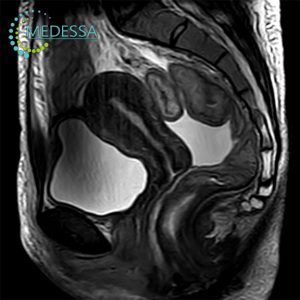

МРТ-діагностика в медичному центрі MEDESSA